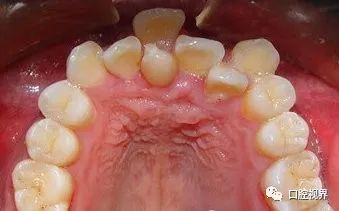

牙位异常(多生牙)

这些情况通常都是容易辨认,一经发现还是尽早前往正规的口腔医院处理一下。

此外,部分小朋友的乳牙没能按时下岗,从而导致牙缝变大,严重甚至还会使得恒牙不能正常萌出。